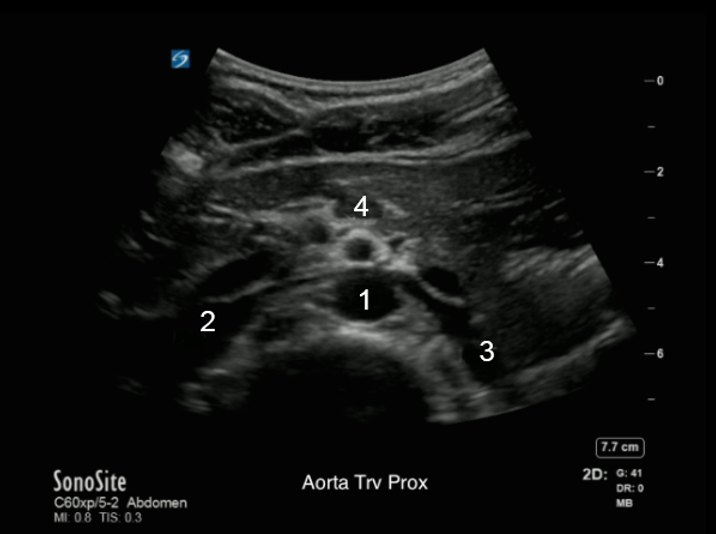

Image - Aorte moyenne, coupe transverse

1. Aorte (Ao)

2. Veine cave inférieure (VCI)

3. Veine rénale gauche

4. Artère mésentérique supérieure